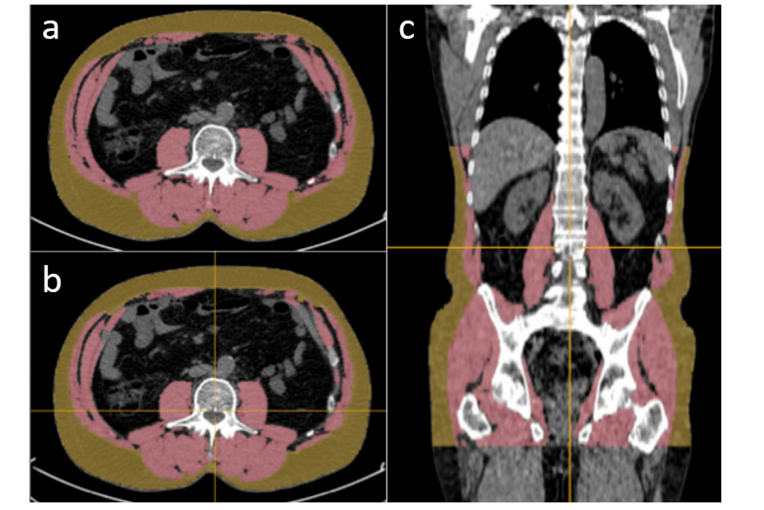

Fig. 1 Manual vs. AI segmentation of SAT and muscle. On a CT slice at L3 level, the left side shows manual segmentation (a) and detailed visualization of AI segmentation (b). A coronal slice demonstrates how the AI-based 3D reconstruction from T11 extends down to the hip bone ©. The measurements reveal that manual areas for SAT amount to 186 cm² compared to approximately 170 cm² for muscle tissue; conversely, AI-based methods measure slightly smaller areas of around 184 cm² for SAT but show even more refined divisions with volumes of approximately 6,832 cm³ for SAT regions compared to nearly identical muscle volumes of about 8,253 cm³._

图1展示了SAT与肌肉组织在手动分割与基于人工智能(AI)辅助分割下的对比。左侧切片显示,在L3水平的CT扫描中分别进行了手动分割(a)与基于AI算法的自动分割(b)。冠状切片展示了从T11到髋骨的基于AI算法生成的人工智能驱动三维分割结果(c)。测量结果表明,在手动分割条件下获得的区域面积分别为SAT 186 cm²、肌肉组织170 cm²;而在基于AI辅助下的区域面积分别为SAT 184 cm²、肌肉组织158 cm²;体积方面,则分别为SAT 6,832 cm³、肌肉组织8,253 cm³。此外,人工智能技术的应用显著提高了对皮下脂肪区域 SAT 的识别精度。